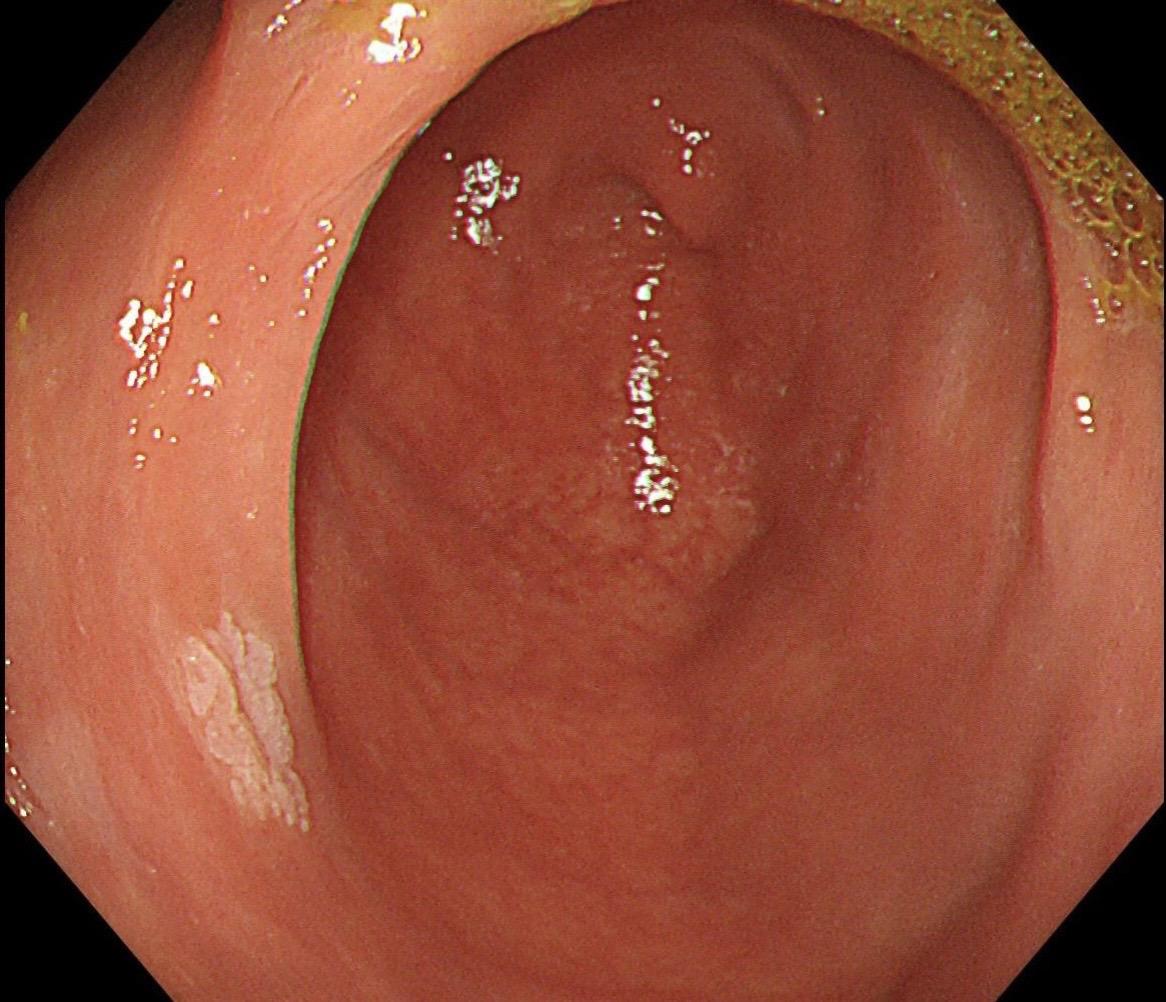

结肠SSL 醋酸染色。染色效果不亚于靛胭脂,结合NBI,Near focus观察表面结构非常OK,下次让护士长买大桶装的,1桶6块9,可以喷一年,哈哈……

结肠SSL 醋酸染色。染色效果不亚于靛胭脂,结合NBI,Near fo...